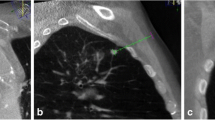

A 69-year-old man with suspected primary lung malignancy. a The intraprocedural non-contrast CT image (using mediastinal soft tissue window) showed a homogenous mass. b 18F-FDG PET/CT imaging showed a mass with uneven uptake (SUVmax = 12.8) (arrow) in the left lower lobe. c CT and prior PET/CT fused image showed FDG-avid peripheral region of the mass were targeted. Final surgery revealed lung large cell carcinoma with central necrosis

A planning CT scan (10-cm range) was performed before percutaneous needle insertion, and then the biopsy system including introducer needle (Cook Incorporated) and BioPince™ full core biopsy instrument (Argon medical devices, INC) was introduced in a stepwise manner under the guidance of images (CT images alone or CT and PET/CT fused images). An appropriate puncture point on a patient’s skin was marked to determine the shortest needle entry route while avoiding the inclusion of bullae and vascular structures. After local anesthesia with 2% lidocaine, a 10-cm-long 17-gauge percutaneous introducer needle was then advanced to puncture from the skin on the marked point without penetrating the parietal pleura. After confirming the direction of the tip of the puncture needle by the second CT scan (1.6 cm range), the needle was advanced further into the lesion (hypermetabolic area on fused images). Then the third CT scan was performed to confirm the final position of the tip of the needle before obtaining specimens coaxially. Two to three specimens were collected by BioPince™ full core biopsy instrument and subjected to histological evaluation for specific diagnosis (Figs. 1, 2). Finally, the fourth CT scan (the entire lung) was performed to rule out the presence of possible complications (e.g. pneumothorax, intrapulmonary hemorrhage, hemothorax, air embolism, etc.) after pulling out introducer needle. The CT-guided biopsy method was consisted with our previous studies. [15, 16] The severity of procedural complications was evaluated according to the Society of Interventional Radiology Standards of Practice Committee classification of complications [17], and procedure duration (defined as the interval time between the initial scout image and the end of the final CT scan) was also recorded. In addition, a repeat biopsy was considered when the patient’s clinical condition was obviously inconsistent with initial biopsy results (two patients) or when chemotherapy or targeted therapy regimens need to be adjusted (twenty patients). However, only the initial procedure result was recorded and analyzed in this study.